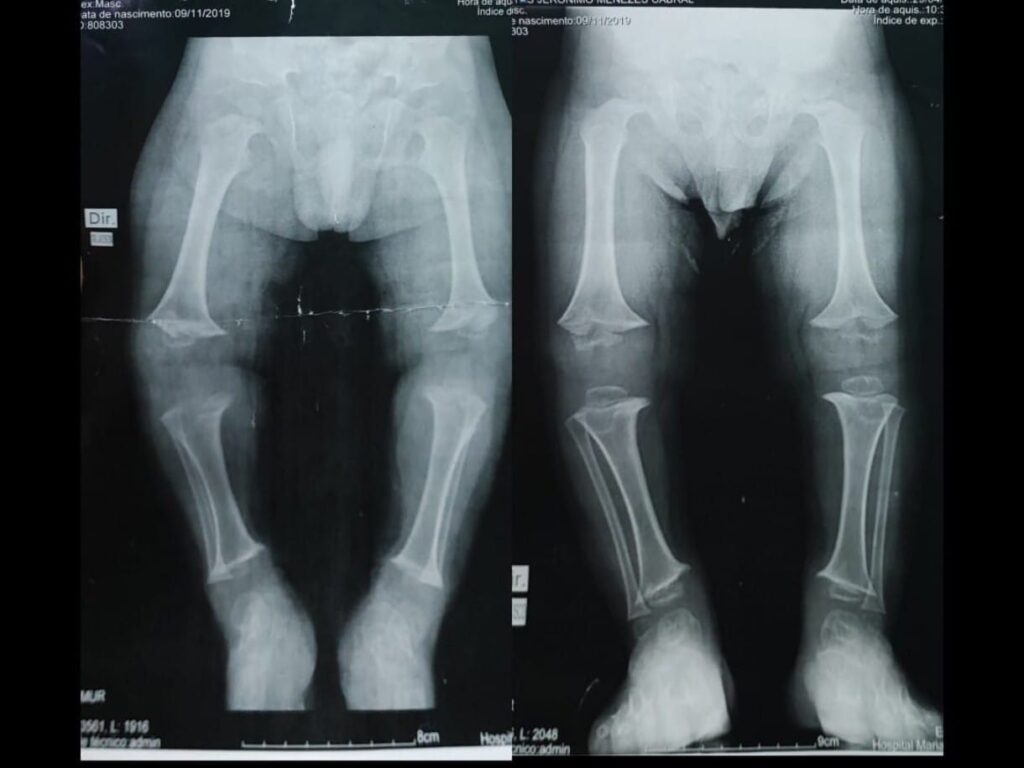

Decorrente de mutações no gene FGFR3, a acondroplasia é a causa mais comum de displasia óssea que leva à baixa estatura desproporcional. Como implica em alterações no desenvolvimento da cartilagem das placas de crescimento, o quadro resulta em baixa estatura. Em média, os homens têm 1,31 m de altura, enquanto as mulheres possuem 1,24 m. Além disso, é comum o encurtamento de pernas e braços, cabeça e testa são proeminentes e há uma desproporção corporal de limitações físicas visíveis já no nascimento.

O desenvolvimento motor é mais lento devido aos membros e pescoço curtos e macrocefalia. A hipoplasia da face média em combinação com hipertrofia da adenóide e das amígdalas pode levar a apneia obstrutiva do sono. A otite média crônica é comum também nesse grupo de pacientes, assim como a perda auditiva. Já a estenose espinhal e lombar, com déficits neurológicos, são mais frequentes na idade adulta, tal como as doenças cardiovasculares. A obesidade também é comum.